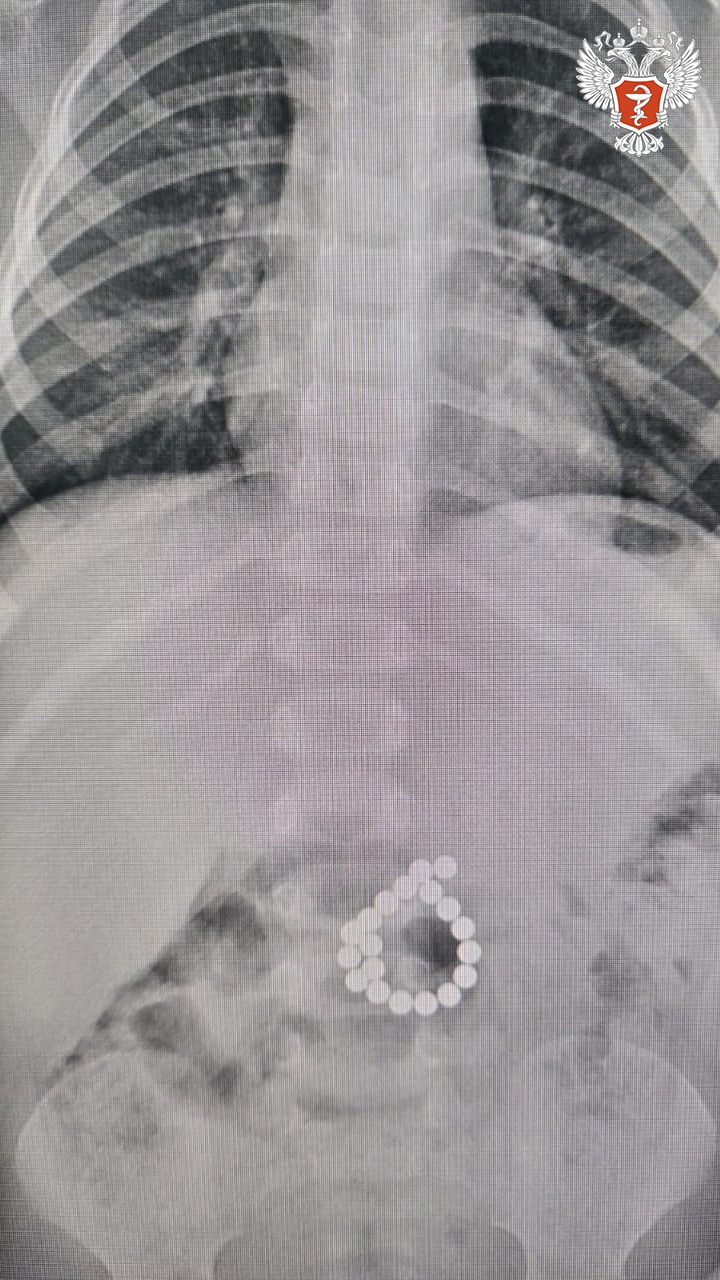

➡ В ходе обследования врачи приняли решение о проведении операции. В ходе хирургического вмешательства в толстой кишке были обнаружены 19 магнитов, которые, притягиваясь друг к другу через стенки кишечника, вызвали сдавление тканей и формирование двойной перфорации. Развилось воспаление брюшной полости — жизнеугрожающее состояние.

Хирурги удалили инородные тела и ушили дефекты кишечной стенки. После операции ребёнок в течение шести суток находился в отделении реанимации, где получал интенсивную терапию, включая парентеральное питание, антибактериальное и обезболивающее лечение, стимуляцию работы кишечника.